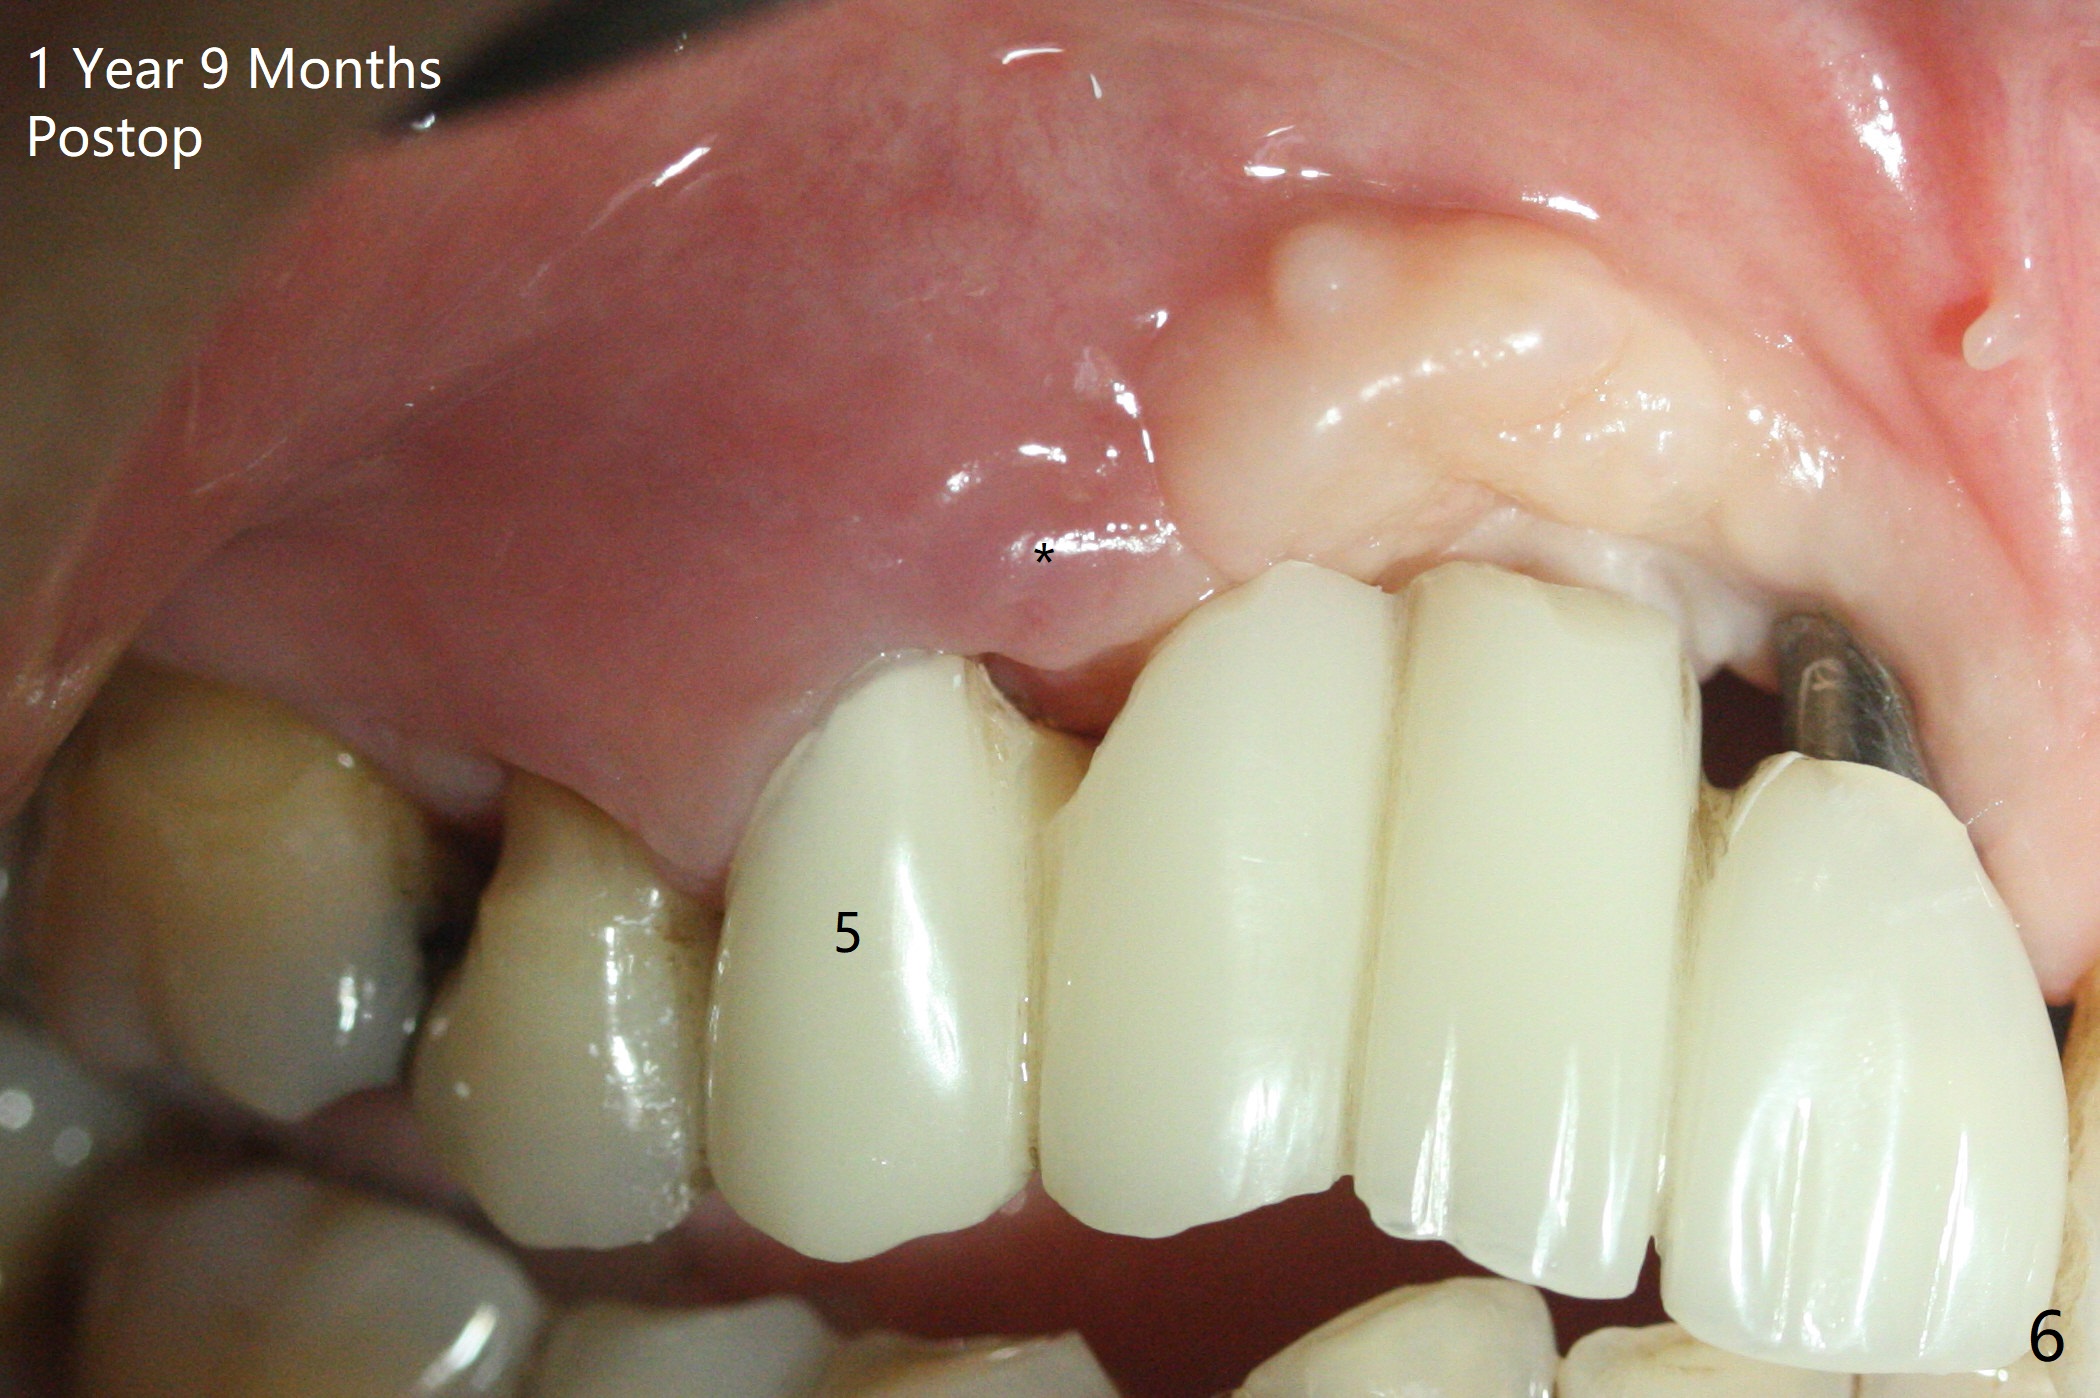

Four months post bone graft with tenting screws at #6 and 7 and implant re-placement at #8, the ridge at #6 and 7 appears to widen slightly, appropriate for narrow implants (Fig.1,2). Guide will be fabricated. The implant at #8 seems to have osteointegrated (Fig.3) with distal gingival recession (Fig.4). One year 5 months later, the tooth #5 is infected with apparently mesial bone loss (Fig.5 *) and papillary erythema and edema (Fig.6). However the pockets are not deep. A gingival embrasure is created between #5 and 6 for self cleansing. The latter does not work. Implants will be placed at #5 and 7 (Fig.7,8).